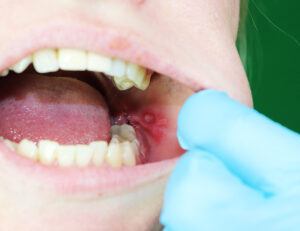

これって大丈夫?歯茎にできる口内炎アップル歯科伊丹駅前。

好きです: 146